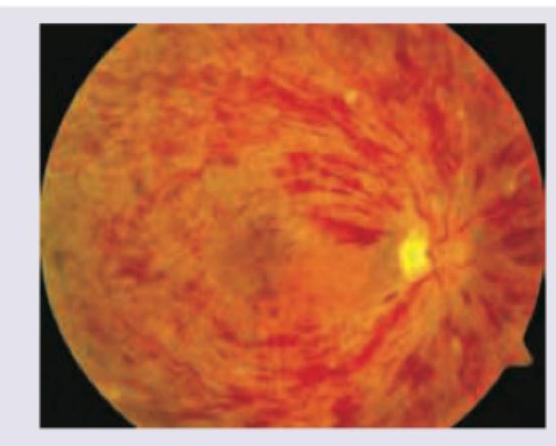

This is the picture of the fundus of a female patient, who was on estrogen containing pills, and presents with sudden deterioration of vision. What is the likely diagnosis?

Explanation: ***Central retinal vein occlusion*** - The fundus image shows widespread **hemorrhages**, **dilated and tortuous veins**, and **optic disc swelling** which are classic signs of central retinal vein occlusion (CRVO). - Estrogen-containing pills increase the risk of **thrombosis**, making CRVO a plausible diagnosis in a patient presenting with sudden vision deterioration. *Diabetic background retinopathy* - While diabetic retinopathy can cause hemorrhages and exudates, the extensive, diffuse hemorrhages and significant venous engorgement seen here are more characteristic of a **venous occlusion**. - Diabetic retinopathy typically presents with microaneurysms, blot hemorrhages, hard exudates, and sometimes cotton wool spots, usually without the widespread venous changes seen in the image. *Hypertensive retinopathy* - Hypertensive retinopathy typically features **arteriolar narrowing**, **arteriovenous nicking**, flame-shaped hemorrhages, cotton wool spots, and sometimes optic disc edema if severe, but not the widespread pan-retinal hemorrhage and venous dilation depicted. - The patient's history does not mention hypertension, making this less likely compared to a thrombotic event linked to estrogen use. *Central retinal artery occlusion* - Central retinal artery occlusion (CRAO) presents with a **pale retina** and a **cherry-red spot** in the macula, due to acute ischemia. - The fundus image provided shows **widespread hemorrhages and dilated veins**, which are not characteristic features of CRAO.